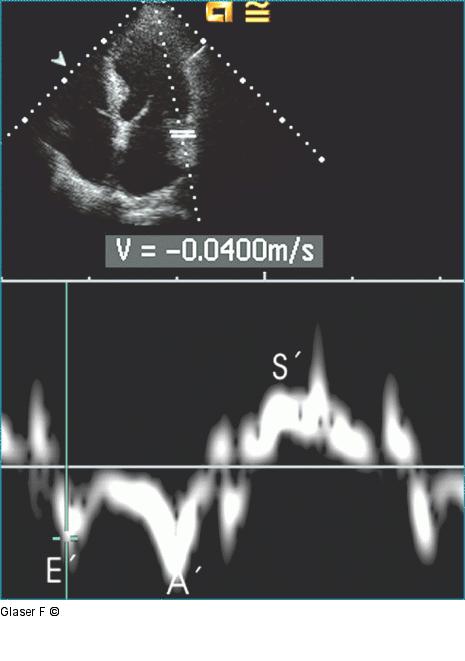

Abbildung 4: Gepulster Doppler Gepulster Gewebedoppler des lateralen Mitralannulus: sehr niedrige frühdiastolische Myokardgeschwindigkeit (E´-Welle). Ein Amplitudenverhältnis von E_mitralis/ E´ von > 15 entspricht einem erhöhten linksventrikulären Füllungsdruck. |

Gepulster Gewebedoppler des lateralen Mitralannulus: sehr niedrige frühdiastolische Myokardgeschwindigkeit (E´-Welle). Ein Amplitudenverhältnis von E_mitralis/ E´ von > 15 entspricht einem erhöhten linksventrikulären Füllungsdruck. |